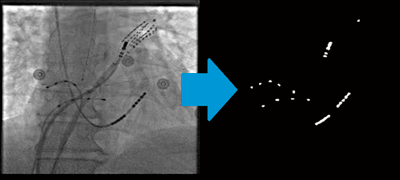

呼吸により横隔膜が動くことで心臓の位置も変化するが,3Dロードマップにおいてこの体動の補正を試みる機能が,GE社独自の“Image Stabilization”である。カテーテルアブレーションの特性を利用し,透視画像においてX線の高吸収体である電極カテーテルを周波数分析することで,リアルタイムに動きを認識しトレースする(図2)。特に,coronary sinus内に留置したカテーテルは,横隔膜の動きと連動しており,そのカテーテルの動きの分だけ3Dロードマップ画像を移動させることで,呼吸体動の影響による3Dロードマップ画像の位置ズレを最小限にすることができる。

図2 Image Stabilization

電極カテーテルの動きをリアルタイムに認識し,トレースすることができる。